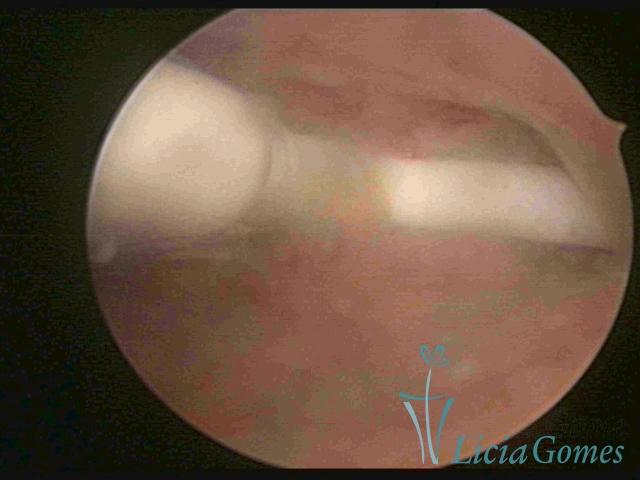

DIU normo inserido